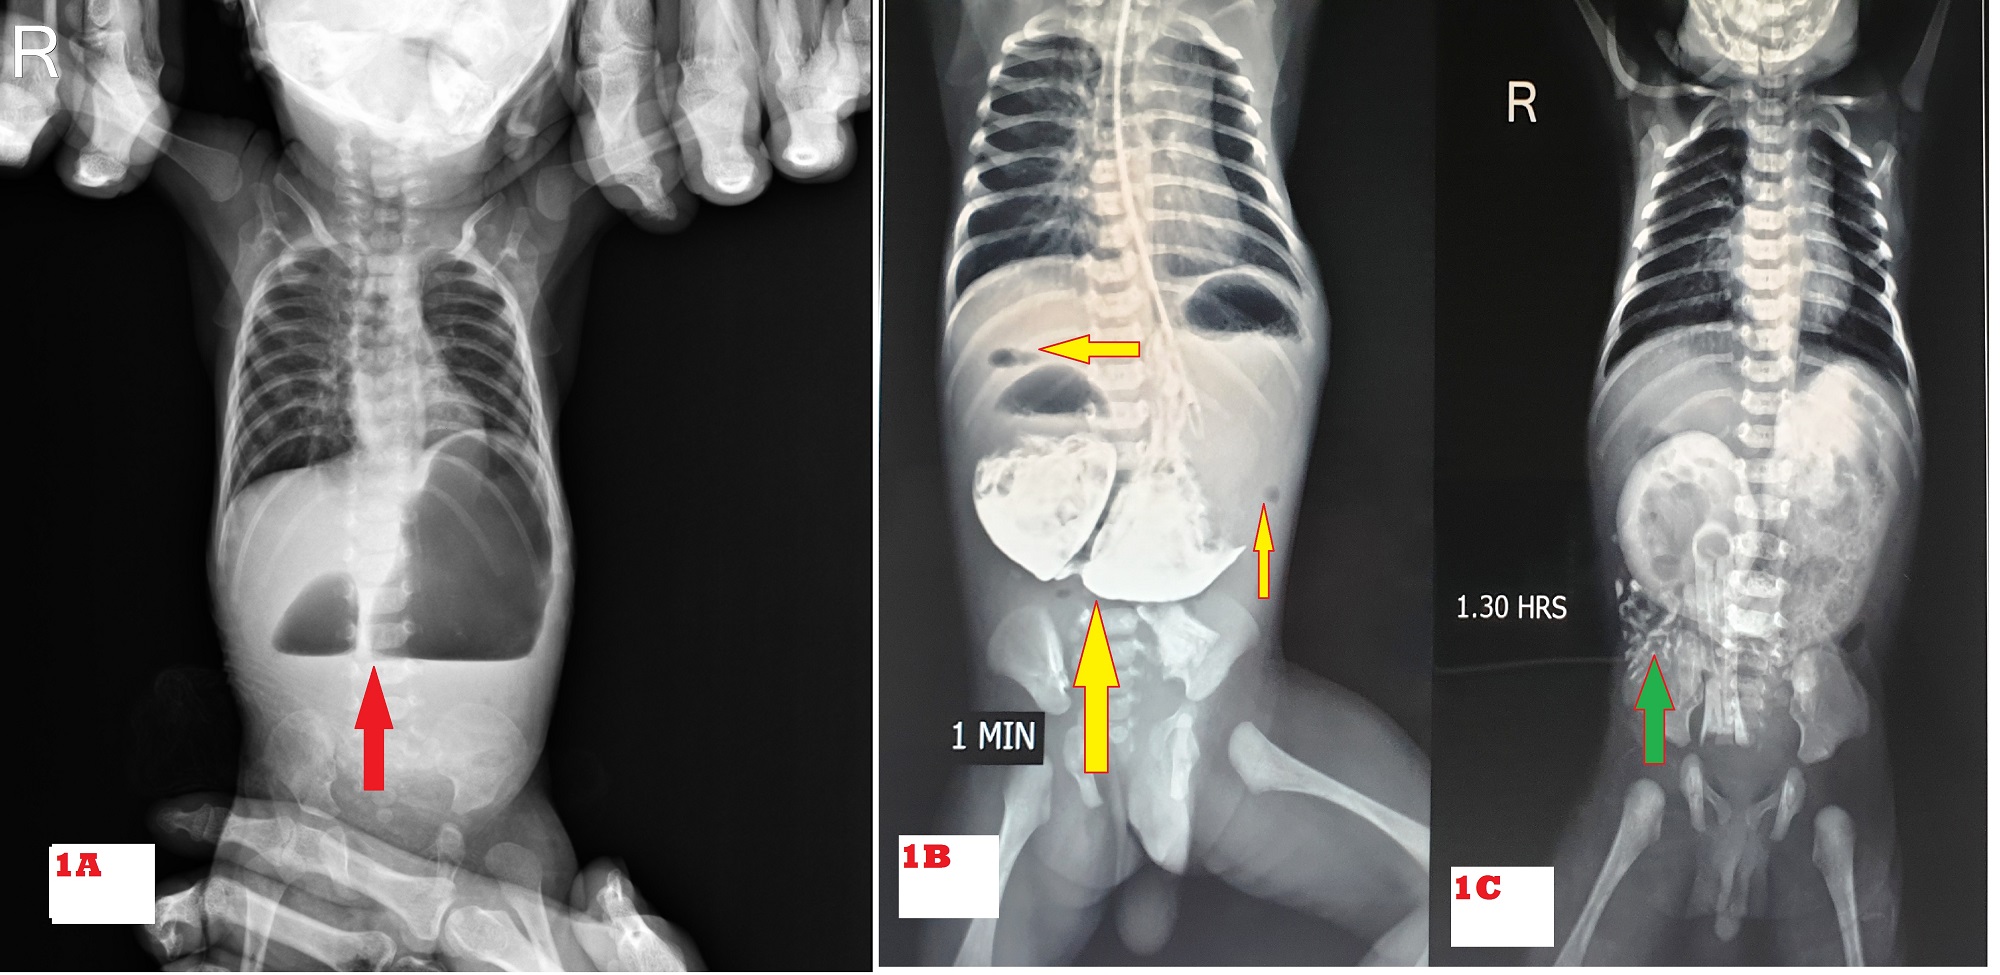

Of 67 patients, 39 were male and 28 were female with a male to female ratio of 1.4:1. The demographic characteristics of the patients are shown in Table. 1. The common presenting features on presentation were vomiting in 59 (88%) of which 44 had bilious and 15 had non-bilious vomiting, and epigastric bulge in 52 (77%) (Fig. 2). Double bubble appearance on X-ray abdomen was seen in 54 (81%) (Fig. 1A). Seven infants had distended stomach and duodenum with gas in the small bowel on abdominal x-ray. Abdominal USG color Doppler was done to rule out malrotation. Six underwent a gastrografin upper GI contrast study which gave suspicion of the perforated duodenal web (Fig. 1B, 1C). One patient underwent Upper GI endoscopy which showed windsock deformity with a small hole on the web along with a foreign body. The inability to insert stiff red rubber catheter beyond 10 cm per orally with double bubble appearance on of babygram was observed in 7 patients. A single bubble was found in 5 cases. In the patient with IEA, the diagnosis of CIDO was made during feeding gastrostomy, in which the infant feeding tube was not negotiable beyond the second part of the duodenum; moreover, the stomach and duodenum were dilated and filled with bile mixed mucus.

Preoperative X-ray abdomen showing a double bubble sign is diagnostic of duodenal obstruction. It was sufficient to diagnose 54 (81%) patients in this study. Duodenal web with hole (centric or eccentric) was diagnosed by gastrografin meal follow-through in 6 patients and in one by UGI endoscopy.

Figure 1

A) Double bubble sign (Red arrow). B & C) Gastrografin upper GI contrast study- hugely dilated stomach and duodenum with intrinsic obstruction as a smooth and rounded end at D2 with distal air (yellow arrow)/ contrast (green arrow) without distal beaking effect into D3.